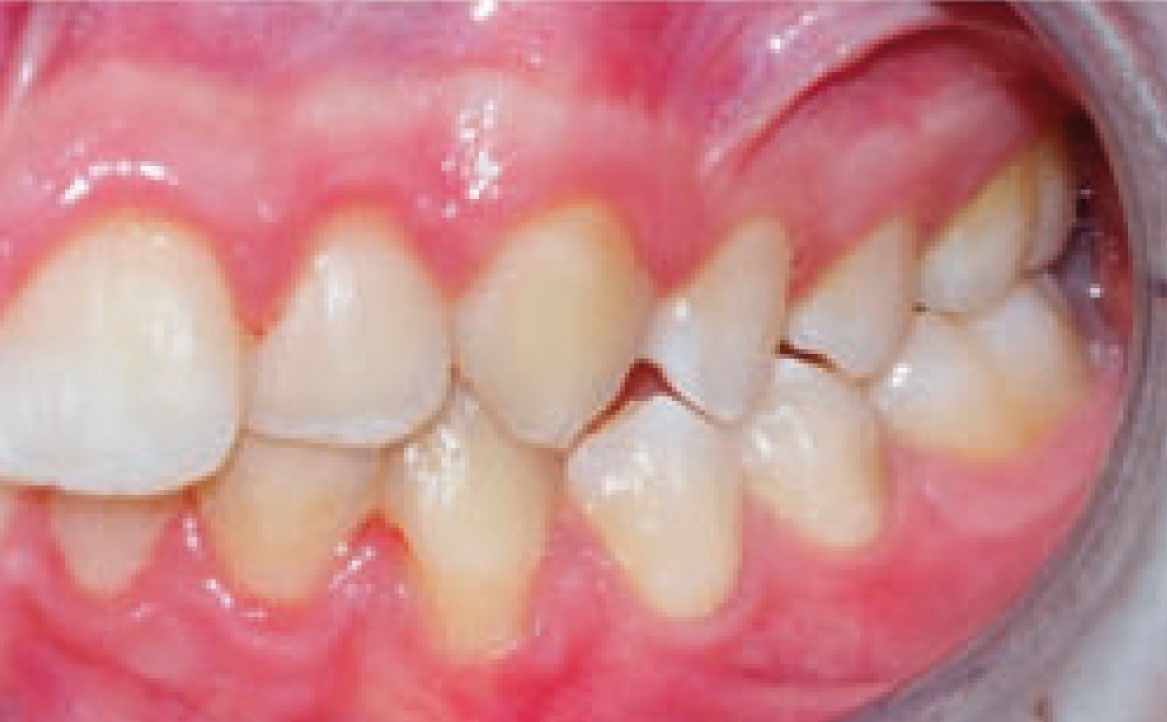

Dall’esame obiettivo intra orale si osservava una seconda classe canina destra e sinistra, una seconda classe molare destra e sinistra, e un diametro inter-canino e inter-molare ridotto sia in riferimento al mascellare superiore sia al mascellare inferiore (fig. 3A-3E).

Clinical examination revealed high caries risk, poor oral hygiene, and constricted upper and lower arches.